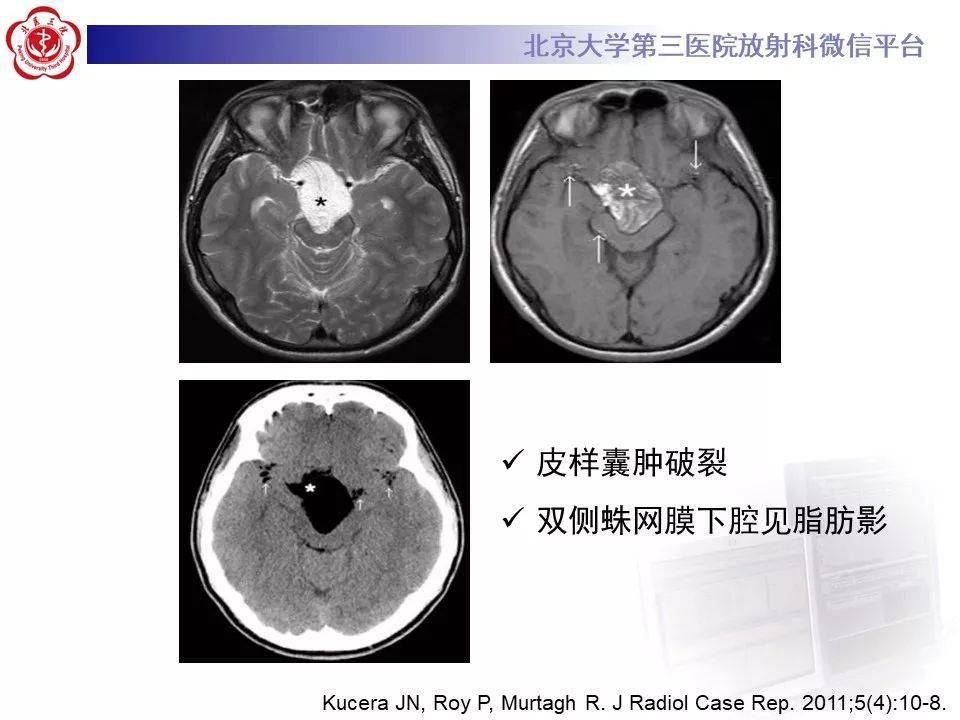

颅内畸胎瘤影像诊断与鉴别